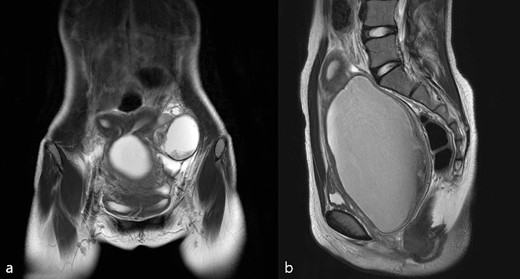

A 14-year-old girl presented to the emergency room with abdominal pain. She started menarche 13 months ago. Her menstrual period was regular, and she usually complained of mild cyclic abdominal pain. She recently experienced progressively increasing dysmenorrhea. On admission, her blood pressure was 135/84 mmHg, 108 beats/min, and her temperature was 37.2°C. Laboratory analysis revealed that the white blood cell count was within normal range. However, the erythrocyte sedimentation rate was elevated to 25 mm/h (normal 0–20 mm/h) and C-reactive proteins to 6.78 mg/l (normal 0–5 mg/l). Tumor markers showed elevated levels of cancer antigen 125 at 57.5 U/ml (normal 0–35 U/ml) and cancer antigen 19–9 at 399.40 U/ml (normal 0–37 U/ml), respectively. Clinical examination revealed a large abdominal mass and diffuse abdominal tenderness. Transabdominal sonography revealed a uterine didelphys. The left uterus showed a hematometra, an ipsilateral adnexal tumor, and a large cystic structure near the left cervical region. Magnetic resonance imaging (MRI) (Fig. 1a and b) showed uterine didelphys. An ~12 cm hematocolpos was formed due to an obstructed hemivagina on the left side, and an ovarian cyst of ~6 cm in size was present in the left ovary. The left kidney was not visualized. Based on these findings, OHVIRA syndrome, also known as Herlyn–Werner–Wunderlich syndrome, was suspected. As of American Society for Reproductive Medicine (ASRM) Müllerian anomalies classification 2021, it corresponds to the uterus didelphys and obstructed left hemivagina. Surgical intervention through hysteroscopy and laparoscopy was performed. First, a hysteroscopic incision of the left bulging hemivagina was performed. First, one vagina and one cervical opening were identified using a hysteroscope, and it was confirmed that the left vaginal wall was bulging. After the hysteroscopic incision of the left hemivagina, dark-colored blood flowed out. Laparoscopy revealed uterine didelphys. In addition, only the left side of the pelvic cavity had severe adhesions, and the left large hematosalpinx with distal tubal obstruction and a cyst of the left ovary contained chocolate-brown fluid and were firmly adhered to the peritoneum and intestines. An ovarian cystectomy and a fimbrioplasty of the left adnexa were performed. According to the revised classification of the American Society for Reproductive Medicine, endometriosis was diagnosed as Stage IV [3]. The histopathology confirmed endometriosis. She was treated orally with 2 mg/day dienogest for only 1 year after surgery and then stopped medical treatment. The last follow-up examination, 3 years after surgery, showed no recurrence of endometriosis.

(a) T2 coronal view, (b) T2 sagittal view of pelvic cavity MRI of Case 1; MRI revealed hematocolpos, hematometra, and ipsilateral ovarian endometriosis.